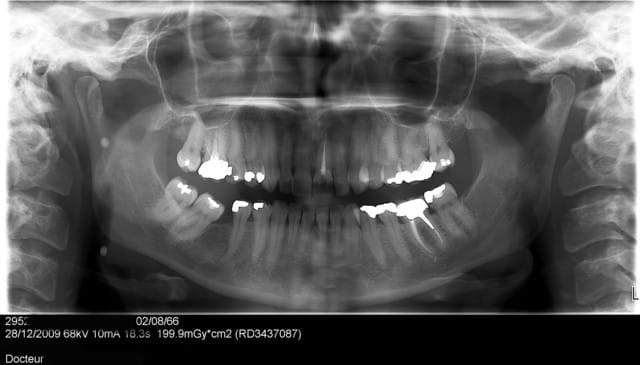

qui va trouver le premier et me dire ce que c'est en réalité que les petits points qu'on voit sur cet opt ?

les 3 points sont régulièrement répartis, est ce que cela continue ainsi jusqu'à ses pieds?

c'est un piège..... c'est sympas la gauche et la droite j'y vois une belle symétrie..enfin presque...ou deux semblables...,...c'est un extra-terrestre....?

Les attaches d'un vêtement type burka ou hiqab que la patiente n'aurait pas retiré lors de la radio...

> des perles sur une tresse de ses cheveux?

OUIIIII !.

bravo, c'est toi qui a gagné !

merci aux fous rires pour les boules de geischa, et la perruque ..